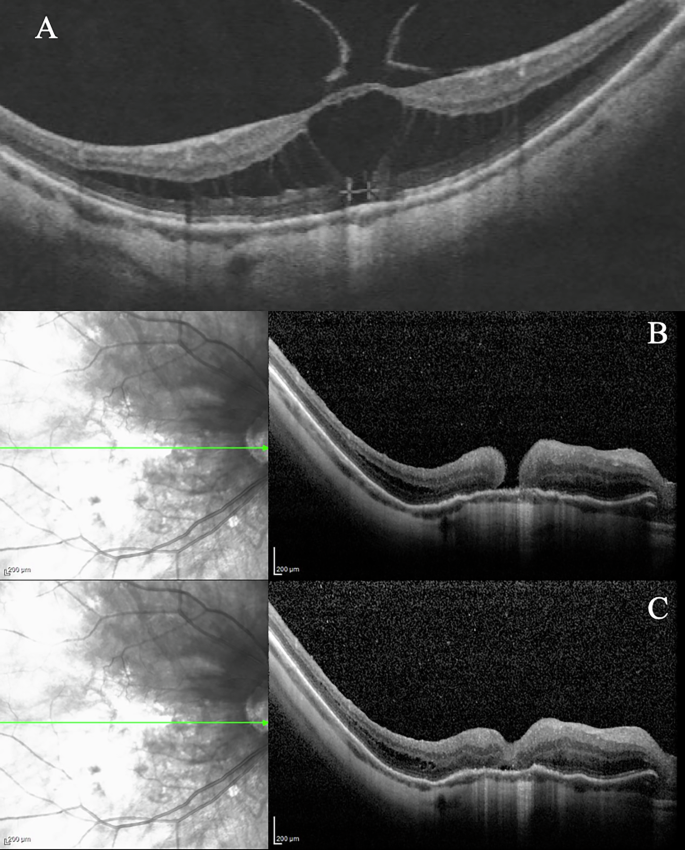

The outcomes of MB in patients with extremely high axial length were investigated in two prospective studies by Bedda et al. [26] and Ma et al. [27]. Bedda et al. evaluated a novel sutureless illuminated MB without adjuvant PPV in 20 MH patients, achieving 100.0% MD resolution but only 40.0% MH closure. No higher rate of exoplant displacement was reported. Ma et al. [27] compared PPV + ILM peeling versus PPV + ILM peeling + MB in 98 patients with extremely high axial length, demonstrating superior anatomical and functional outcomes with the latter. A successful case of PPV + ILM peeling + MB from our experience is illustrated in Fig. 3.

A Preoperative OCT showing a case of MD with tangential traction with a BCVA of 0.1 decimals. B OCT of the same case 2 years after MB + PPV; BCVA at follow up was 1.0 decimals. BCVA best corrected visual acuity, ILM inner limiting membrane, MB macular buckling, MD macular detachment, OCT optical coherence tomography, PPV pars plana vitrectomy.